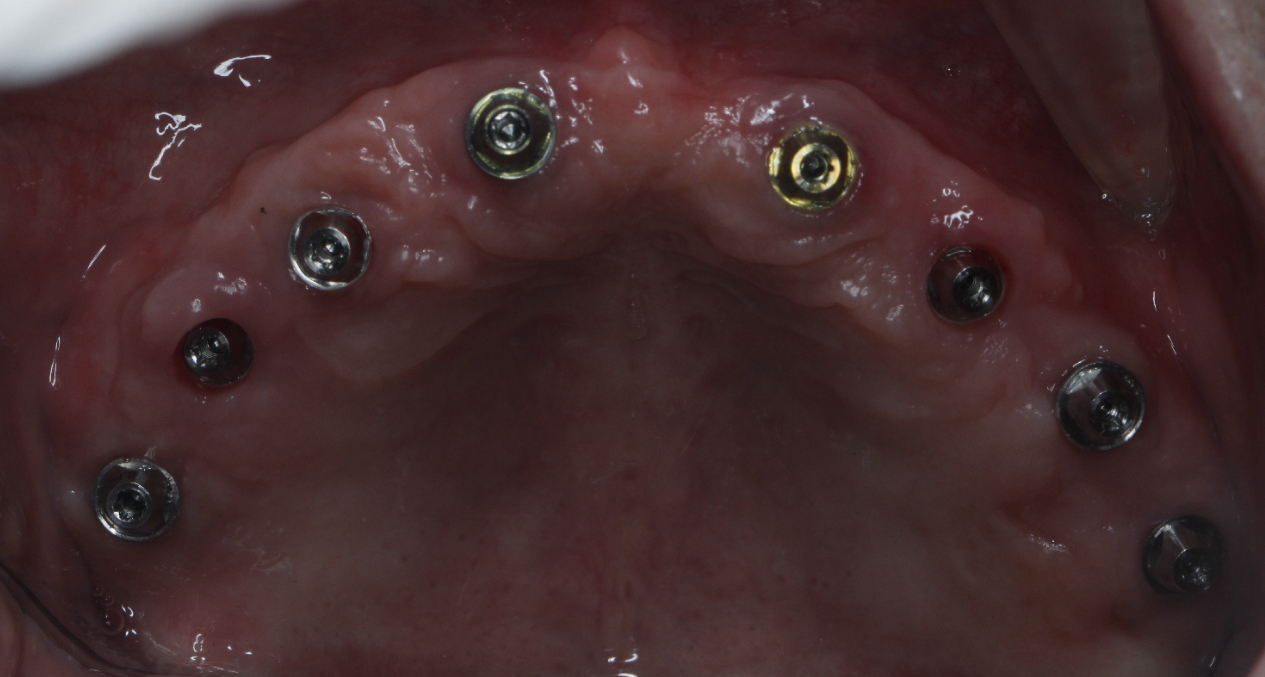

该患者就是因牙周病导致牙齿松动脱落,我们通过在半口牙槽骨上植入8颗种植体,然后在种植体上安装连桥牙冠,从而恢复半口牙齿的咀嚼功能和美观。相对于传统的种植修复方式缺一颗种一颗。4-8颗种植体的种植手术创伤相对较小,大大的减少了患者的疼痛感。